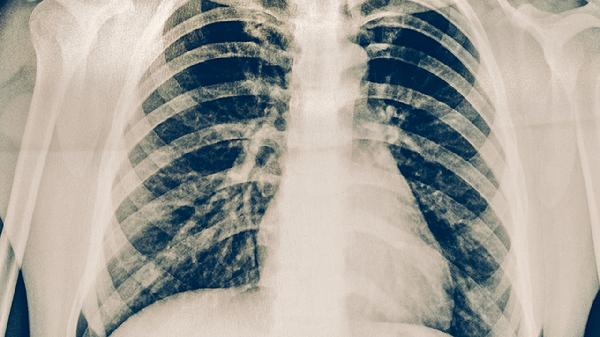

右心衰竭型肺病是從病理生理角度對(duì)肺心病的描述,強(qiáng)調(diào)右心室負(fù)荷過重的特征。長(zhǎng)期肺動(dòng)脈高壓使右心室后負(fù)荷增加,最終導(dǎo)致心肌收縮力下降。臨床可見劍突下心尖搏動(dòng)增強(qiáng)、三尖瓣區(qū)收縮期雜音等體征,治療需使用利尿劑減輕心臟負(fù)荷,必要時(shí)給予強(qiáng)心藥物。

繼發(fā)性肺動(dòng)脈高壓性心臟病是肺心病的病理學(xué)命名,突出肺動(dòng)脈高壓的核心機(jī)制。慢性缺氧引發(fā)肺血管重塑,血管壁增厚導(dǎo)致肺動(dòng)脈壓力持續(xù)升高。診斷需排除原發(fā)性肺動(dòng)脈高壓,治療重點(diǎn)包括長(zhǎng)期家庭氧療、肺動(dòng)脈擴(kuò)張劑應(yīng)用等延緩疾病進(jìn)展。